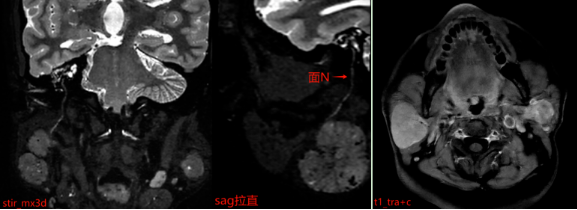

MR表现:双侧腮腺浅叶下极见结节状略混杂信号,T1以低信号为主、T2以 稍高信号为主,DWI呈稍高信号,ADC图呈稍低信号,边界清晰,增强扫描病变中等强化,强化较均匀,其内见点状无强化影。

报告中特别提到“加扫stir_mx3d序列”,这一步骤非常重要。该序列能更清晰地显示病变与周围神经、血管的解剖关系。腮腺区域内走行着重要的面神经,它控制着我们的面部表情肌肉。如果手术中损伤该神经,可能导致术后面瘫,影响患者闭眼、微笑等基本功能。